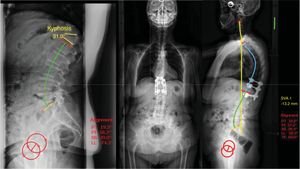

In the group with compensated flexible angular kyphosis (1 A C), if a stable curve is present, vertebroplasty (VP)/kyphoplasty (KP) can be performed to correct the flexible kyphosis and provide anterior stability. In the case of posterior wall involvement or pedicle fracture, resulting in instability, a short cemented instrumentation should be added to provide stability.7 If the flexible angular kyphosis is not compensated (1 A NC) and there is sagittal imbalance due to proximal thoracic hyperkyphosis, Ponte or facet flexion osteotomies may be necessary and long instrumentation up to the upper thoracic spine (T2–5) would be necessary to prevent pathology at the adjacent level (Fig. 5).

Illustration of a case with stage 1 A NC, in which, without the need to perform a three-column osteotomy, very good intraoperative reduction is observed and long percutaneous T4-L2 instrumentation and vertebroplasty of L3, L4, and L5 is performed due to fractures at that level. 1 A NC: deformity secondary to angular, flexible and non-compensated osteoporotic vertebral fracture.